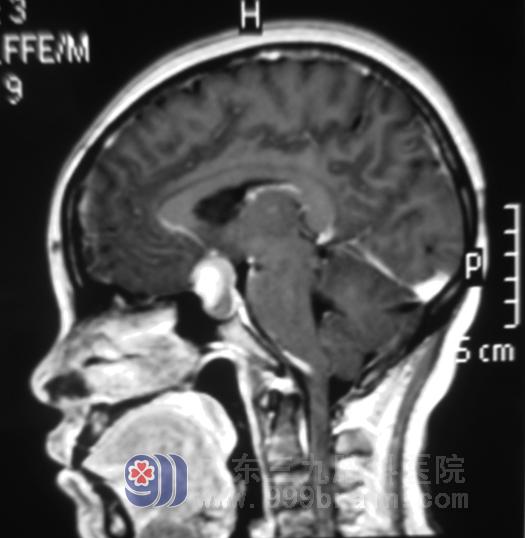

这回可不敢再大意,李姐及家人马不停蹄地来到广东三九脑科医院垂体瘤诊疗中心。头颅MR见肿瘤大小约为2.0×?xml:namespace>

手术前